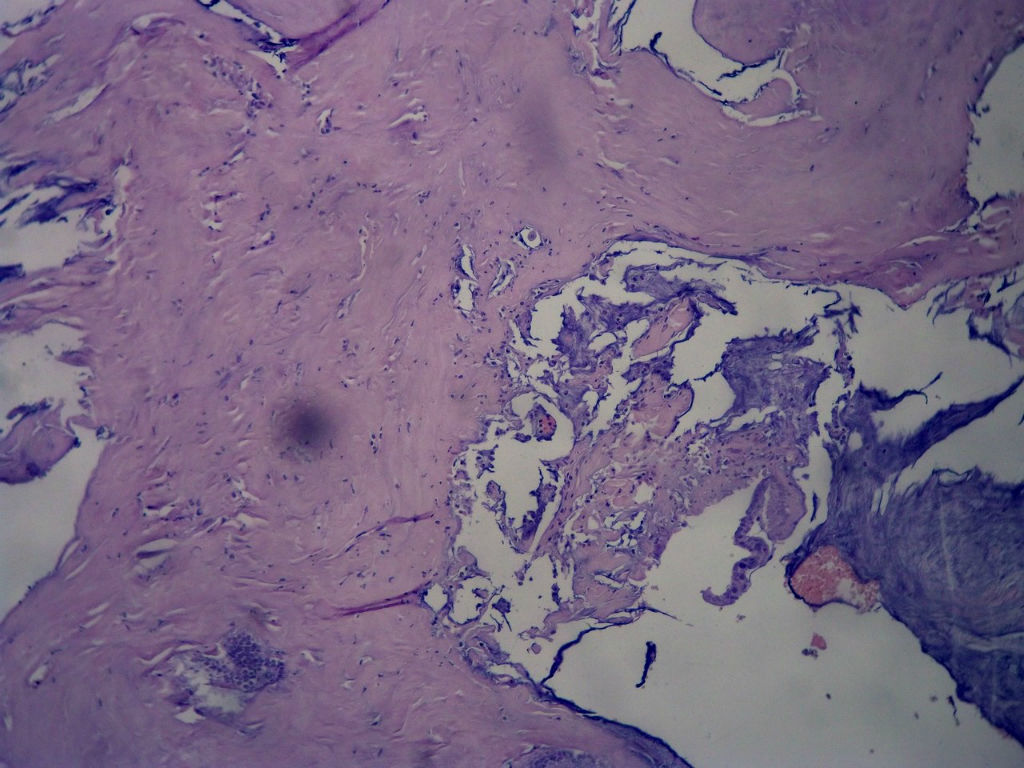

女,80岁,阑尾区肿块。

送检为不规则组织多块,粘滑,解剖结构辨认不清。术中探查双侧卵巢无异常。

• 女,80岁,阑尾区肿块。图4

图4

阑尾粘液性肿瘤,癌的可能性大

粘液长在肌层,而且漂浮着可疑上皮细胞,最大可能粘液腺癌。